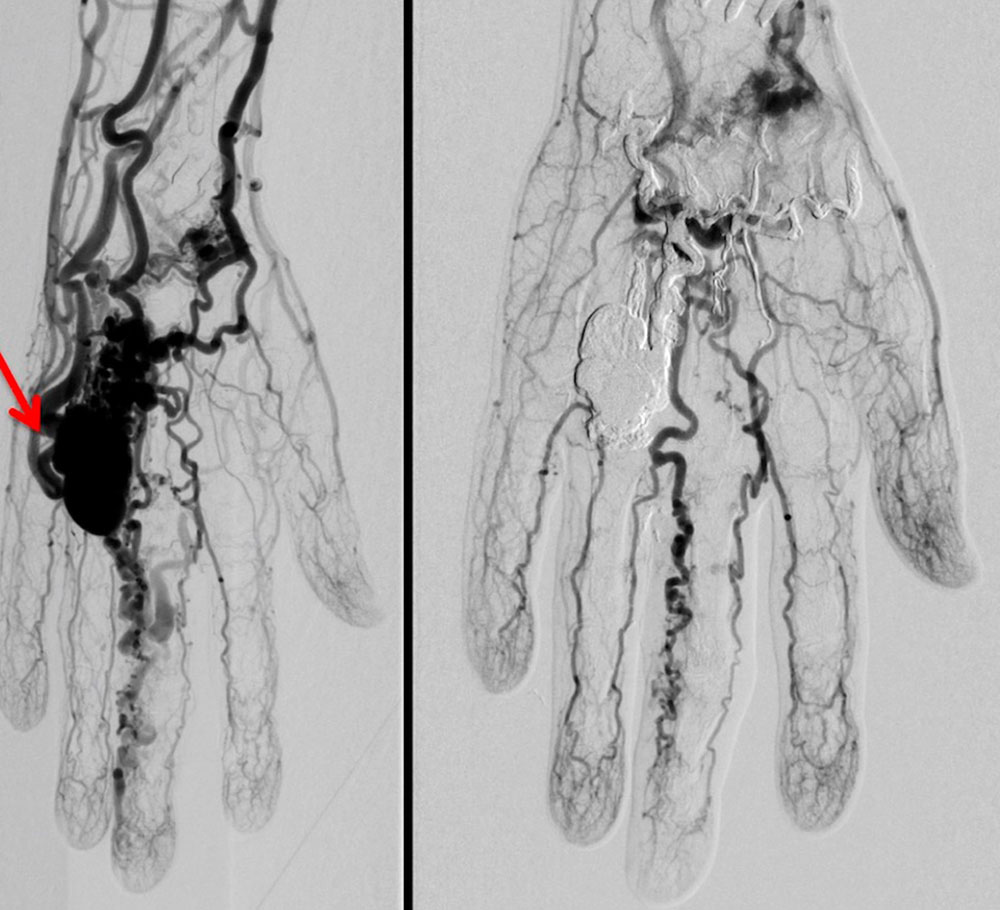

Die perkutane Embolisation ist nach wie vor die Therapie der ersten Wahl. Bei sehr großen arteriovenösen Malformationen müssen mehrere Behandlungssitzungen geplant werden. Über einen transarteriellen Zugang, eine Angiographie werden der Nidus sowie die frühen Drainagevenen der arteriovenösen Malformation mit permanenten Flüssigembolisaten verschlossen. Als Flüssigembolisate werden Ethylen-Vinyl-Alkohol-Kopolymere, N-butyl cyanoacrylat (nBCA) sowie in seltenen Fällen auch hochprozentiges Ethanol appliziert.

Da die arterielle Versorgung des umliegenden, nicht betroffenen Gewebes geschont werden muss und eine Embolisatverschleppung in gesunde Gefäße absolut zu vermeiden ist, erfordert die Applikation des Embolisats eine große Erfahrung des Anwenders. Lässt es die Angioarchitektur der arteriovenösen Malformation zu, dass nur wenige Drainagevenen vorliegen, so ist eine Embolisation über einen retrograden transvenösen Zugang oder einen direkten perkutanen Zugang perkutane Katheterembolisation eine sehr erfolgversprechende Alternative.